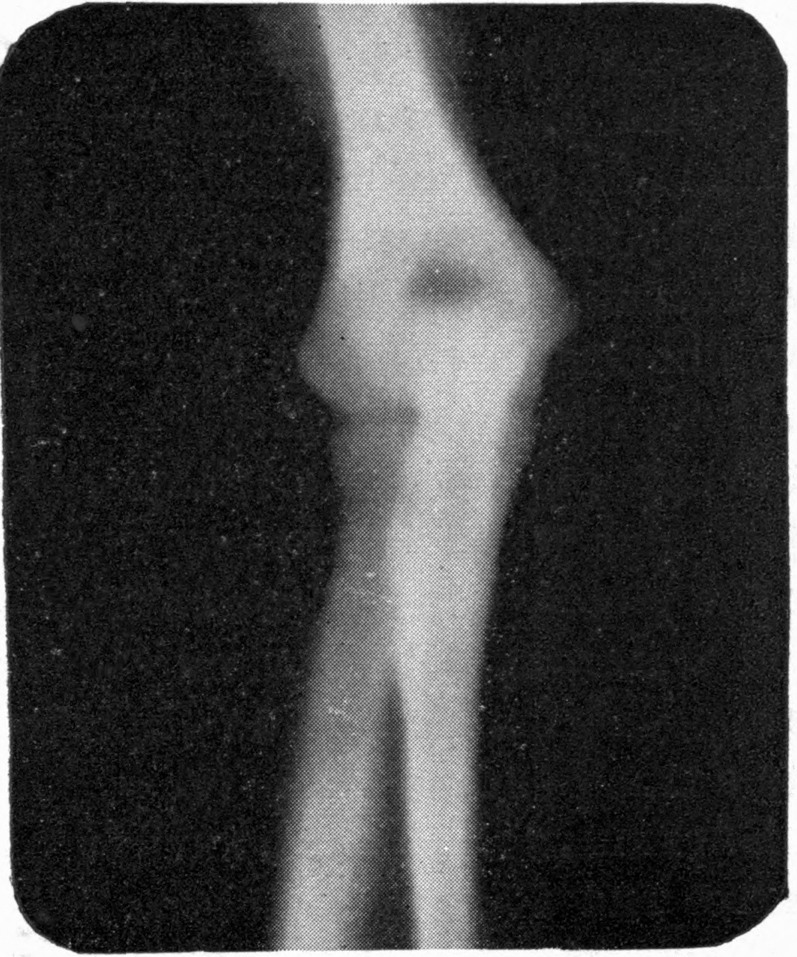

Fig. 1.—Head.

Fig. 2.—Broken Arm, Overlapping.

(Due to defective setting.)

Fig. 3.—Ribs.

Fig. 4.—Knee, Knickerbocker Buttons, Bullet in Femur.